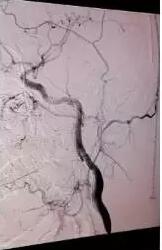

根據(jù)尹先生的病情,張主任先對(duì)其進(jìn)行了藥物治療,積極完善腦血管造影,確診尹先生腦梗死是由于頸動(dòng)脈栓子形成及脫落引起,同時(shí)頸動(dòng)脈夾層導(dǎo)致重度血管狹窄,如果繼續(xù)撕裂或破裂,隨時(shí)會(huì)有生命危險(xiǎn)。經(jīng)過(guò)病情討論后,張主任決定采用“頸動(dòng)脈支架植入+血管成形”,覆蓋夾層,改善狹窄血管。手術(shù)歷時(shí)1個(gè)多小時(shí),并取得成功,治療非常滿(mǎn)意。二十天后,坐著輪椅來(lái)的尹先生,健步走出了醫(yī)院,語(yǔ)言功能、肢體偏癱等均恢復(fù)正常。

前與術(shù)后圖片對(duì)比(左圖術(shù)前  右圖術(shù)后)